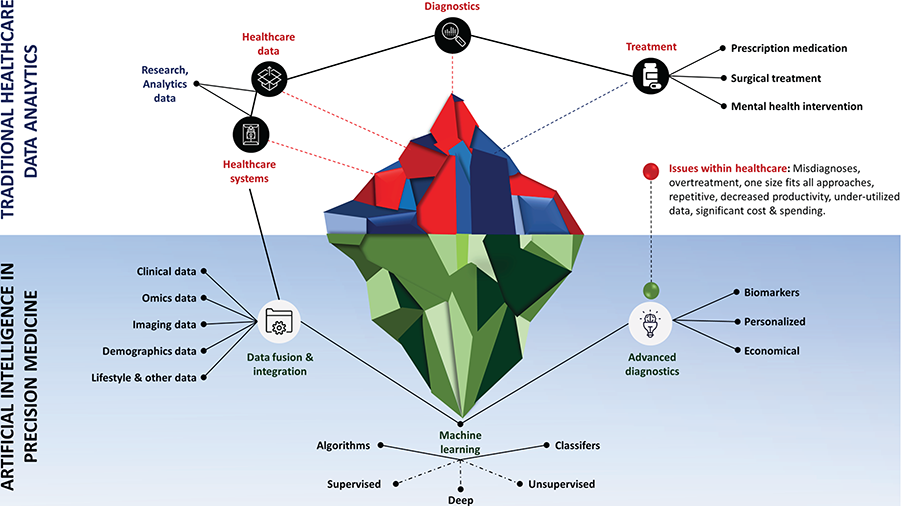

AI is relevant to many healthcare areas including visually-orientated specialties such as radiology, pathology, ophthalmology, and dermatology due to the availability of large digital datasets. Deep learning algorithms leverage these datasets to train themselves and perform a specific tasks e.g. identifying a lesion in an image (Kulkarni et al., 2020). Precision medicine has the potential to improve the traditional symptom-driven practice of medicine by intelligently integrating multi-omics profiles with clinical, imaging, epidemiological and demographic details to allow a wide range of earlier interventions for advanced diagnostics and tailoring better and economical personalized treatment. Below figure depicts the role of artificial intelligence in traditional healthcare data analytics, and in precision medicine(Ahmed et al., 2020).

由于大量数字数据集的可用性,人工智能与许多医疗保健领域相关,包括以视觉为导向的专业,例如放射学,病理学,眼科和皮肤病学。 深度学习算法利用这些数据集进行自我训练并执行特定任务,例如识别图像中的病变(Kulkarni等人,2020年)。 精密医学可以通过将多组学概况与临床,影像学,流行病学和人口统计学信息进行智能集成,从而改善传统的症状驱动医学实践,从而为早期诊断和更广泛,更经济的个性化治疗提供广泛的早期干预措施。 下图描绘了人工智能在传统医疗数据分析和精密医学中的作用(Ahmed等人,2020)。